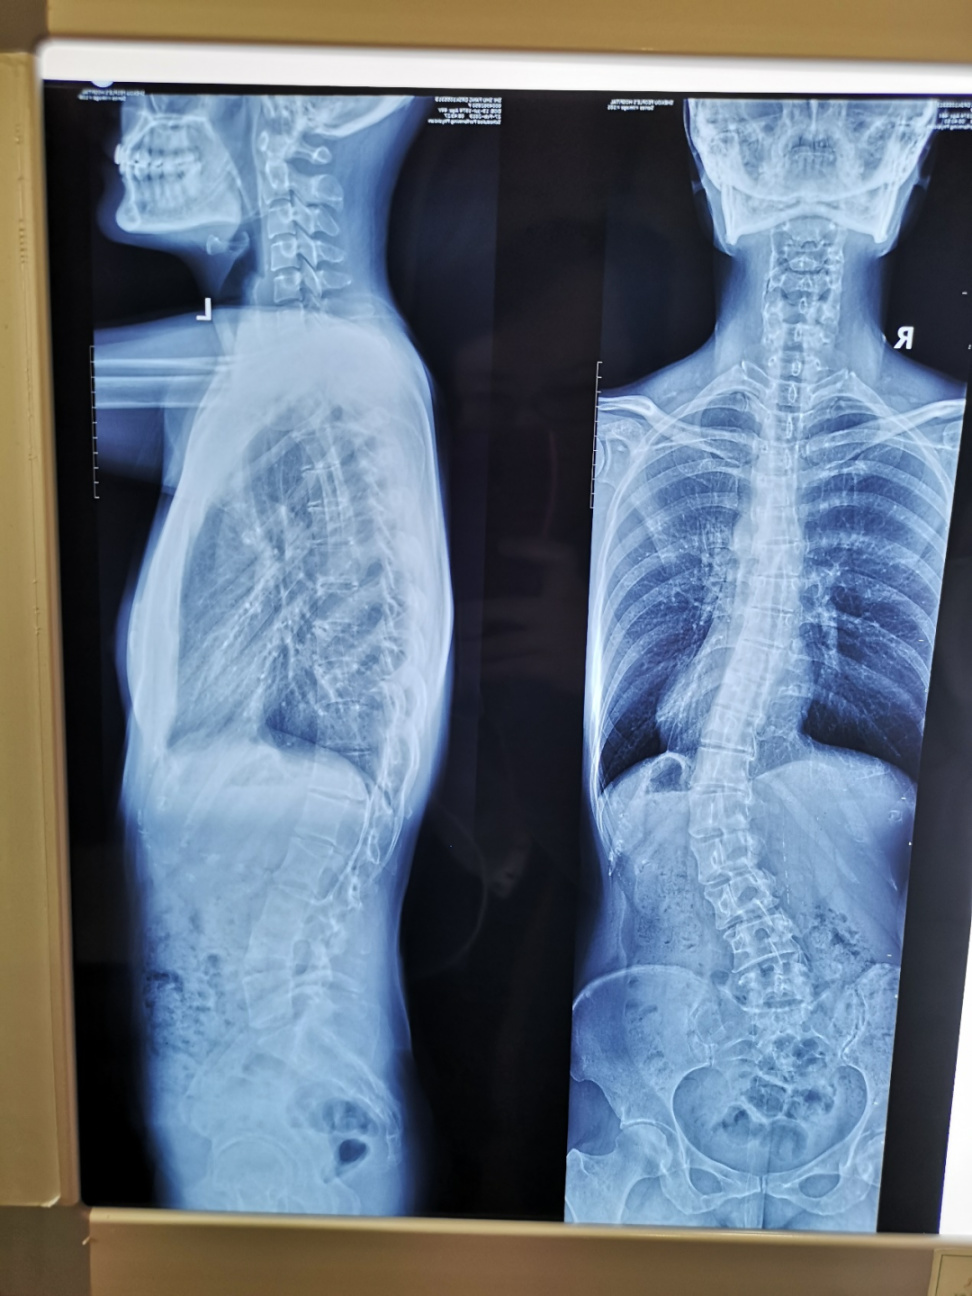

結果到醫院拍片一看:脊椎側彎45度,這個程度非常嚴重。我找遍了骨科名醫,醫生們的結論恨一致:要動手術,如果不動手術,大概半年到兩年的時間裏,我就會大小便失禁,乃至癱瘓。

於是2018年底,我徹底離開了龍圖,也告別了遊戲圈,專心尋找康復之路。